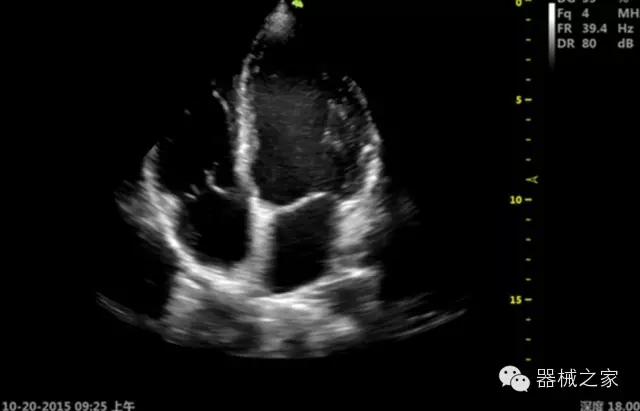

品牌:開(kāi)立(SONOSCAPE)

深圳開(kāi)立生物醫(yī)療科技股份有限公司作為中國(guó)民族醫(yī)療產(chǎn)業(yè)的優(yōu)秀引導(dǎo)者,自成立伊始,一直致力于臨床醫(yī)療設(shè)備的研發(fā)和制造,產(chǎn)品涵蓋醫(yī)用數(shù)字超聲診斷系統(tǒng)、電子內(nèi)窺鏡系統(tǒng)、全自動(dòng)五分類血液細(xì)胞分析儀以及自主研發(fā)的探頭群。

官方網(wǎng)站:www.sonoscape.com.cn

經(jīng)典產(chǎn)品:S8EXP

臨床圖片賞析

產(chǎn)品特點(diǎn)

優(yōu)異的成像技術(shù)

·亞陣元技術(shù):獨(dú)有的亞陣元技術(shù),對(duì)獨(dú)立晶片做二次切割,減少旁瓣偽像,增加臨床診斷的準(zhǔn)確性;

·μ-Scan微米成像技術(shù):開(kāi)立獨(dú)有的μ-Scan技術(shù),還原出真實(shí)細(xì)膩、層次對(duì)比優(yōu)異的二維圖像;

·倒相諧波成像技術(shù):倒相諧波技術(shù)在去除基波信號(hào)的基礎(chǔ)上獲取兩倍二次諧波信號(hào),提高組織圖像的對(duì)比分辨力;

·智能微血流成像技術(shù):智能微血流捕捉技術(shù)可以提取出隱藏在背景噪聲中的弱血流信號(hào),大大提高低速血流的敏感性;

全面的臨床解決方案

超聲科常規(guī)領(lǐng)域應(yīng)用

·移植S40高端臺(tái)式彩超高端平臺(tái)技術(shù),滿足超聲科腹部、淺表、婦產(chǎn)科、心血管、肌骨等應(yīng)用,提供超聲科完美解決方案;

·實(shí)時(shí)的彈性成像技術(shù):提高了小器管(乳腺,甲狀腺、淺表軟組織腫瘤等)疾病鑒別診斷;

·IMT血管內(nèi)中膜自動(dòng)測(cè)量:為血管性疾病評(píng)估提供了有效的評(píng)估手段;

·心功能綜合指數(shù)(TEI指數(shù)):用于左、右心室整體心臟收縮舒張功能評(píng)估的測(cè)量方法;

·全方位可調(diào)M型:有利于更好的觀察心腔大小及室壁階段性運(yùn)動(dòng)的異常情況;

·組織多普勒成像(TDI):TDI可定量評(píng)價(jià)心肌運(yùn)動(dòng),判斷是否有局部病變,還可評(píng)價(jià)早期的舒張功能;

·高效3D/4D成像技術(shù):高速的4D幀頻,豐富的3D成像模式,智能斷層切片功能;

POC領(lǐng)域解決方案

·外觀小巧;

·穿刺增強(qiáng)技術(shù):可有效提高進(jìn)針區(qū)圖像分辨率,提高進(jìn)針亮度,全面提高一次性穿刺的成功率;

全面的術(shù)中探頭解決方案

·小凸探頭:開(kāi)放性手術(shù),實(shí)時(shí)監(jiān)測(cè)病灶位置,提高手術(shù)成功率,可應(yīng)用于麻醉科、肝膽外科、腫瘤外科、神經(jīng)外科、泌尿外科等手術(shù);

·L型線陣探頭:高分辨率圖像,清晰顯示病灶位置,提高手術(shù)成功率,可應(yīng)用于麻醉科、胸外科、肝膽外科、腫瘤外科、神經(jīng)外科、泌尿外科等應(yīng)用;

·MPTEE:經(jīng)食道探頭術(shù)中監(jiān)測(cè),可測(cè)量心臟前負(fù)荷(左室舒張末期大小、右房大小)、心排血量、后負(fù)荷、收縮功能、室壁運(yùn)動(dòng)分析、肝靜脈血流(與中心靜脈壓相關(guān))等,術(shù)后還能及時(shí)評(píng)估手術(shù)效果評(píng)估;

·獨(dú)有的大角度及實(shí)時(shí)溫控技術(shù),能同一切面顯示宮頸及宮體,有效減低了患者的痛苦,及保護(hù)粘膜保證了醫(yī)療安全;

高效的人機(jī)工程學(xué)設(shè)計(jì)

·15‘’高清醫(yī)用顯示器;

·內(nèi)置雙探頭接口;

·可升降臺(tái)車,1拖3探頭擴(kuò)展器;

·m-Tuning一鍵優(yōu)化;

CFDA注冊(cè)證編號(hào)

·粵食藥監(jiān)械(準(zhǔn))字20132230491